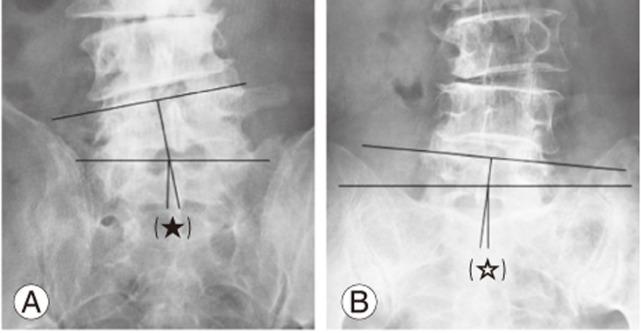

Minimally Invasive Transtubular Endoscopic Decompression for L5 Radiculopathy Induced by Lumbosacral Extraforaminal Lesions.

This study aimed to evaluate the efficacy of minimally invasive transtubular endoscopic decompression for the treatment of lumbosacral extraforaminal lesion (LSEFL).

Conventional procedures for surgical decompression for the treatment of LSEFL involve certain technical challenges because the lumbosacral extraforaminal region has unique anatomical features. Moreover, the efficacy of minimally invasive procedures performed via the posterolateral approach for LSEFL has been reported.

Twenty-five patients who had undergone minimally invasive transtubular endoscopic decompression for the treatment of LSEFL and could be followed up for at least 1 year postoperatively were enrolled. Five of these patients had a history of lumbar surgery, and seven had concomitant adjacent-level spinal stenosis. The clinical outcomes were evaluated using the Japanese Orthopaedic Association (JOA) lumbar score, numeric rating scale (NRS), and the JOA Back Pain Evaluation Questionnaire (JOABPEQ). The mean postoperative follow-up (FU) duration was 3.8 years.